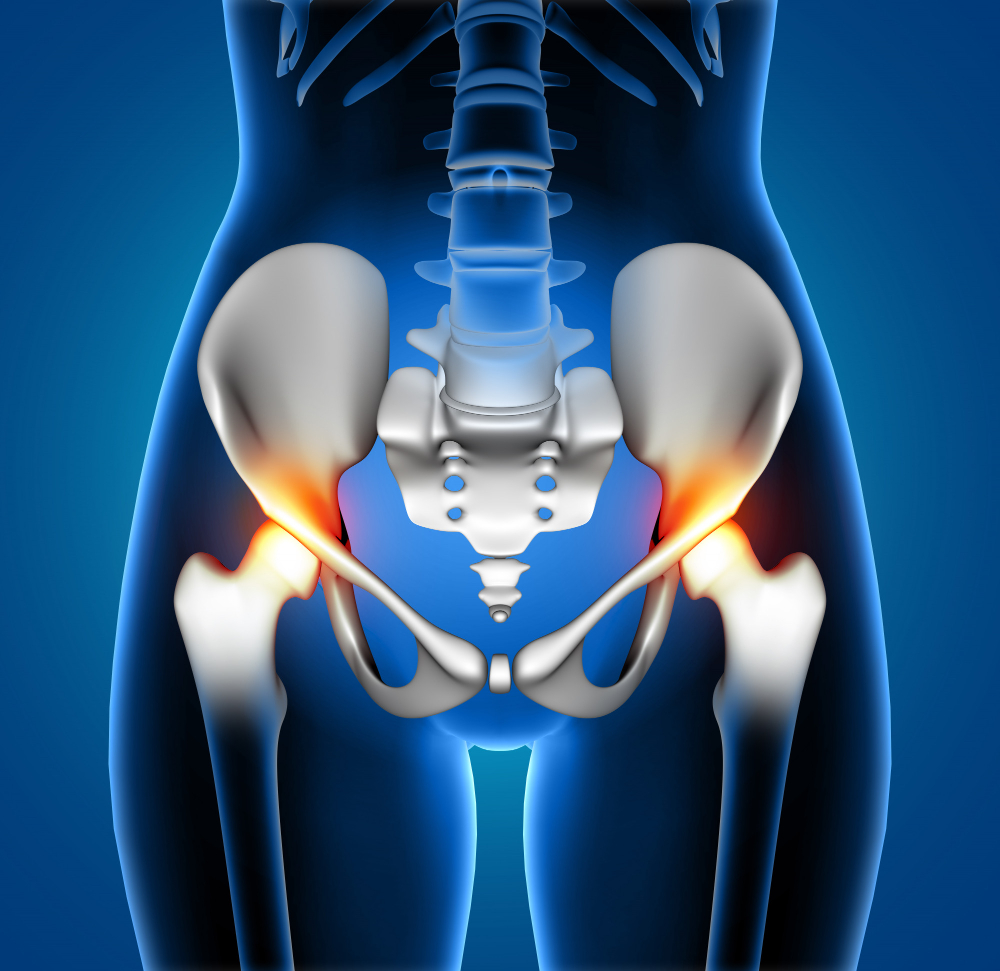

Hip pain can significantly affect your quality of life, limiting mobility, disrupting daily routines, and preventing you from enjoying even simple activities. For many patients, surgery is often presented as the ultimate solution. However, before committing to an invasive procedure like hip replacement, it’s important to explore modern, less invasive alternatives. At RegenOrthoSport, advanced regenerative therapies are transforming the way we approach Regenerative Medicine for Hip Pain, offering effective, non-surgical solutions designed to restore function and reduce pain naturally.

Understanding Hip Pain and Its Causes

Hip pain can arise from various conditions, including osteoarthritis, labral tears, tendon injuries, bursitis, and sports-related trauma. Traditionally, severe cases often led patients toward surgical interventions. While surgery may be necessary in certain situations, it comes with risks, long recovery times, and significant costs.

Today, innovations in Regenerative Medicine for hip pain are providing new hope. These therapies focus on healing damaged tissues rather than replacing them, making them an appealing option for those seeking a safer and more natural recovery.

Surgery is not always the only path forward. In fact, many patients can benefit from Non-Surgical hip Treatment that addresses the root cause of pain without invasive procedures. Regenerative therapies aim to stimulate the body’s natural healing process, reducing inflammation and promoting tissue repair.

One of the most promising advancements in regenerative orthopedics is Stem Cell Therapy for hip pain. This treatment involves using the body’s own stem cells to repair damaged cartilage, ligaments, and tissues within the hip joint.

If you are experiencing persistent hip pain, reduced mobility, or discomfort that interferes with daily life, it may be time to explore advanced options. Conditions that respond well to Regenerative Medicine for hip pain include:

- Osteoarthritis

- Hip labral tears

- Tendonitis

- Sports injuries